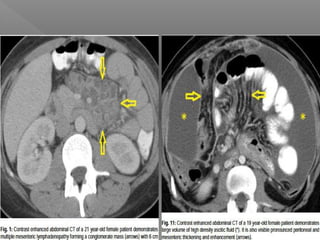

 CT Abdomen

Investigations  CT Abdomen Better than USG for detecting  High density ascites  Lymphadenopathy with caseation  Bowel wall thickening  Irregular soft tissue densities in omental area  Tuberculosis of liver & spleen